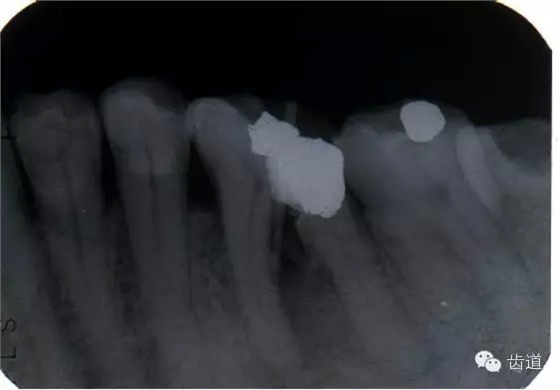

左上5牙頸部側(cè)穿

左下6底穿

左上6底穿

左上4鑄造樁側(cè)穿